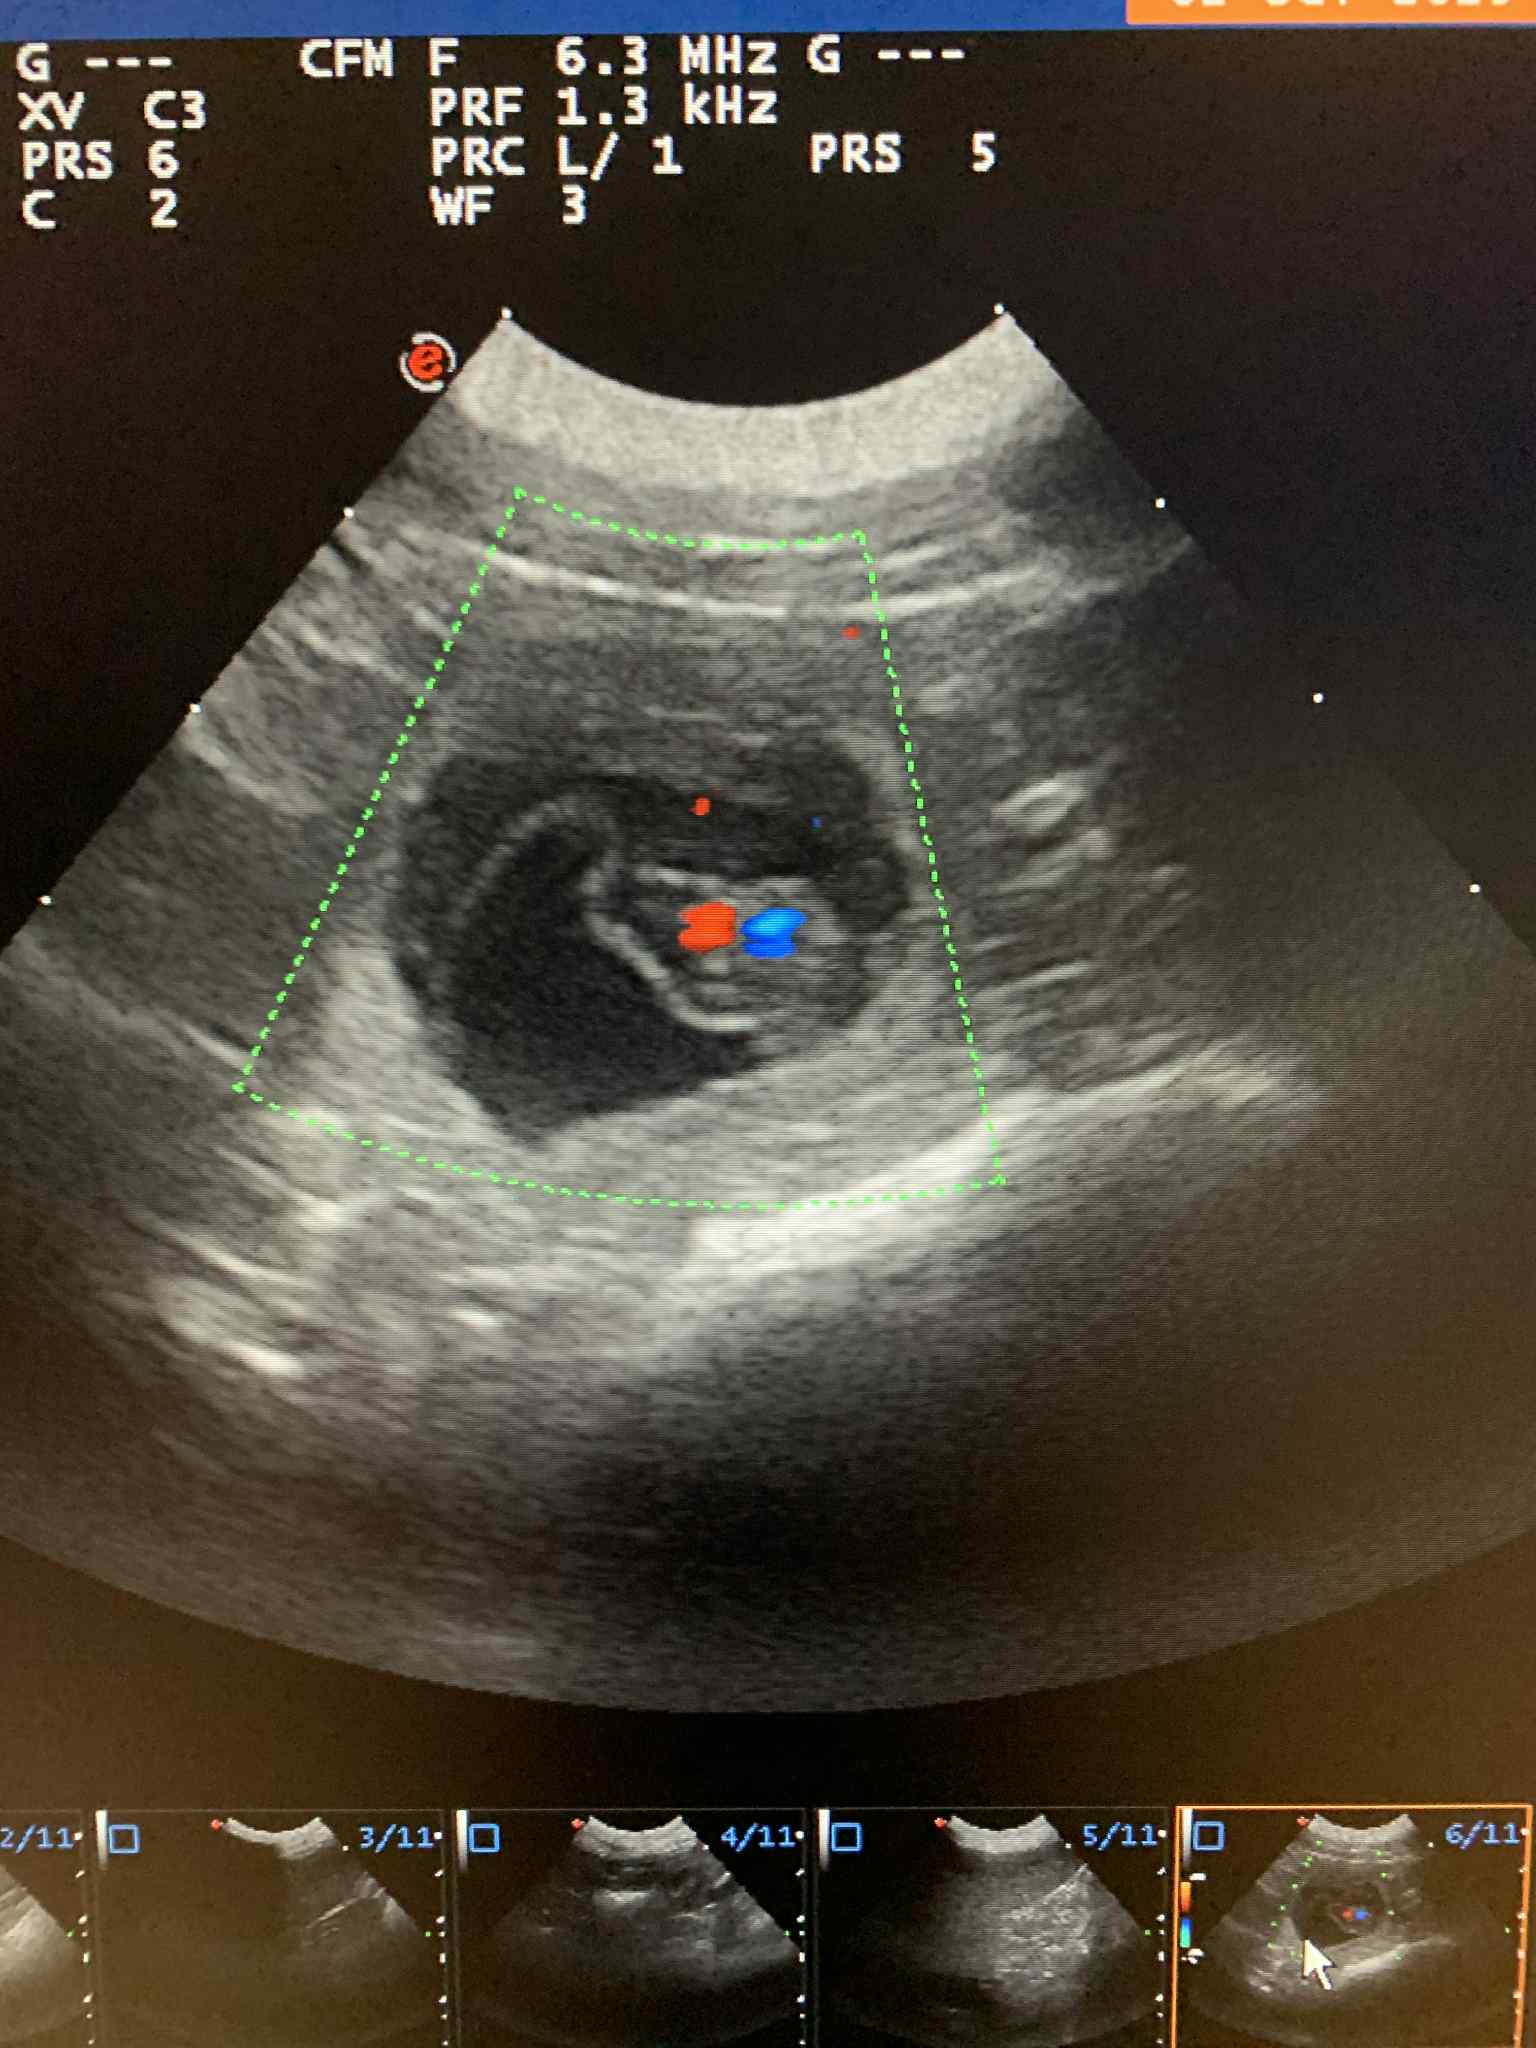

Březost Ziry potvrzena!

Ultrazvuk ukázal minimálně 4 štěňátka a my se moc těšíme!